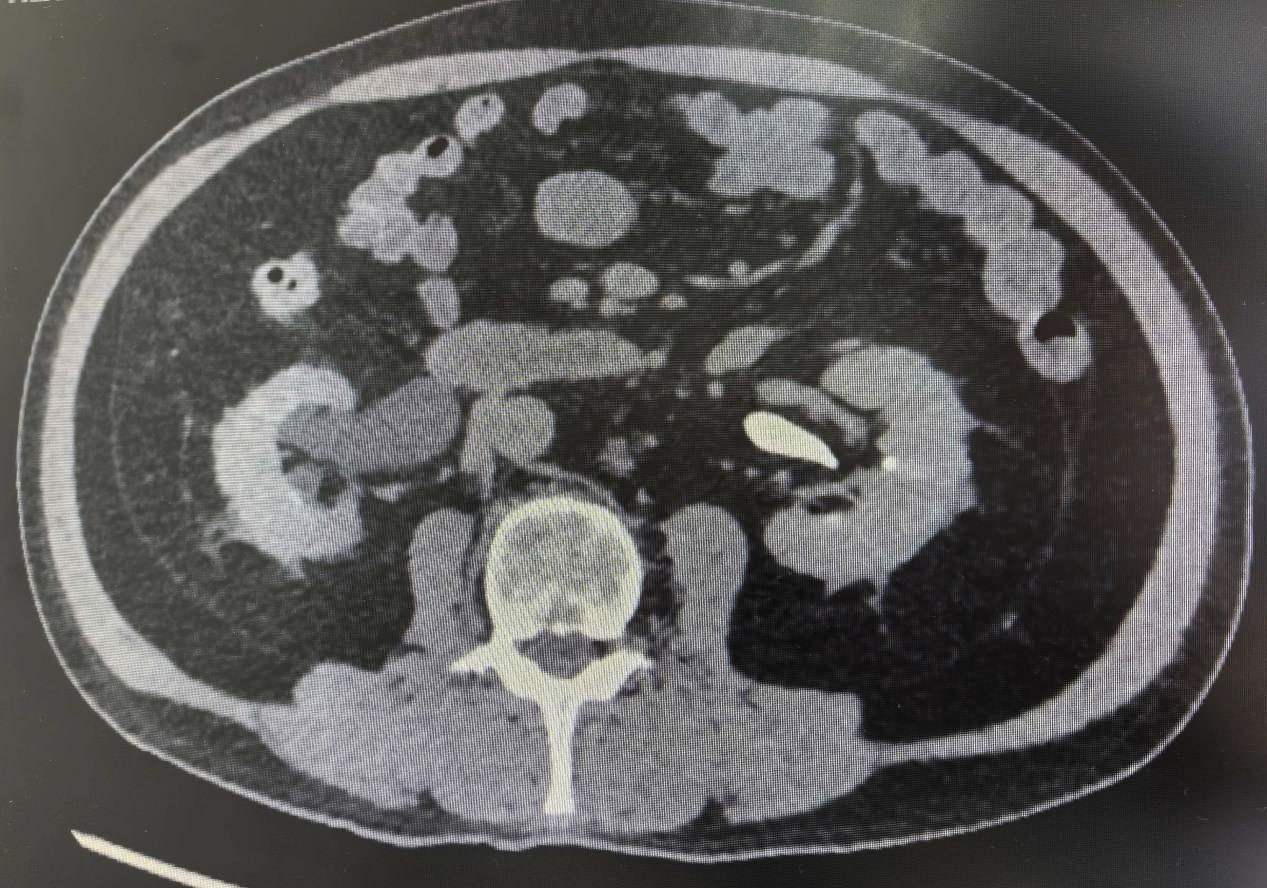

其中,来自湖南的钟先生(化名)一个月前在例行体检中发现右肾存在占位性病变,后经进一步检查确诊为右肾肿瘤,亟需手术干预。出于对桂林医院品牌技术的高度信任,他专程从外地赶来,希望寻求一种既能切除肾脏肿瘤又能保留肾脏功能的治疗方案。

在各项准备工作就绪的情况下,赵洪青教授带领泌尿外科团队,借助达芬奇机器人手术系统卓越的微创与精准优势,为两名患者实施了达芬奇机器人辅助下腹腔镜肾癌根治术。手术过程非常顺利,肿瘤被完整切除。这不仅实现了出血量少、切除彻底的目标,更重要的是最大限度地保留了正常的肾组织,将对肾功能的影响降到了最低。